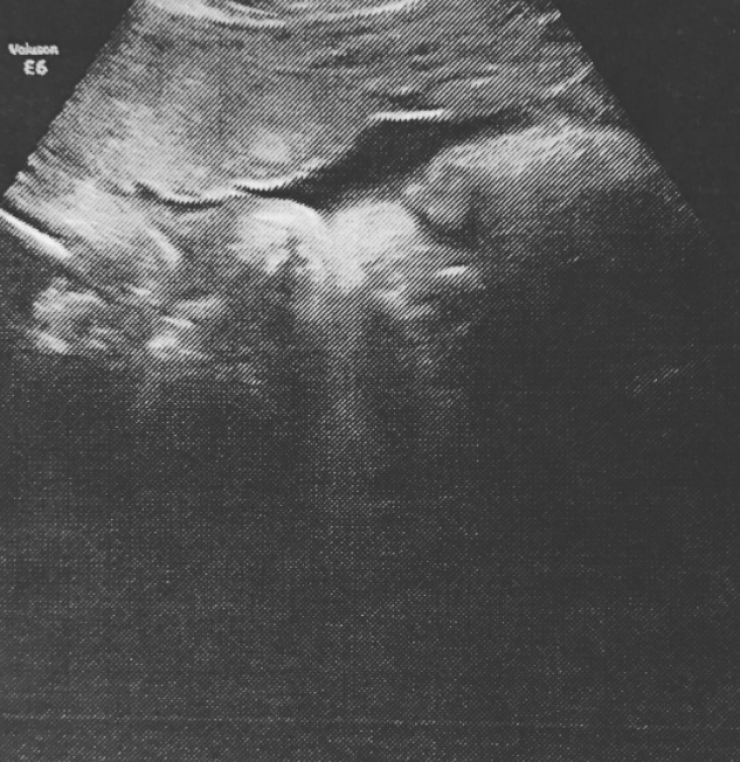

Ο λόγος για τον συμμετέχοντα στη σειρά Glee, Matthew Morrison και τη σύζυγό του, Renee, η οποία μάλιστα μοιράστηκε με τους διαδικτυακούς της φίλους, το υπερηχογράφημα λίγο μετά την αποχώρηση από τον γυναικολόγο της.

Στη λεζάντα που συνόδευσε την εικόνα, έγραψε: “Αυτή η φατσούλα... είναι το μόνο που έχω από τον μικρούλη Μο. Μπορείς να το πιστέψεις; Το χέρι του πάνω στο πρόσωπο όπως πάντα και φυσικά πιπιλάει τον αντίχειρά του... Τόσο αναπαυτικά στην κοιλίτσα της μαμάς... Πραγματικά τώρα, έχω από ένα πόδι σε κάθε άκρη της κοιλιάς μου. Χαλαρώνει... Μα τι είναι αυτή η αγάπη; Αυτά τα έντονα συναισθήματα που κάνουν το μέσα μου να θέλει να εκραγεί; Έπρεπε να μοιραστώ τη φωτογραφία του... Είναι τόσο γλυκός... Εγώ και ο μπαμπάς του δεν μπορούμε να περιμένουμε άλλο.. Ο μπαμπάς έκλαψε μόλις είδε τη φατσούλα του... Περίμενε μπαμπά!!! Περίμενε μέχρι να έρθω στον κόσμο!”